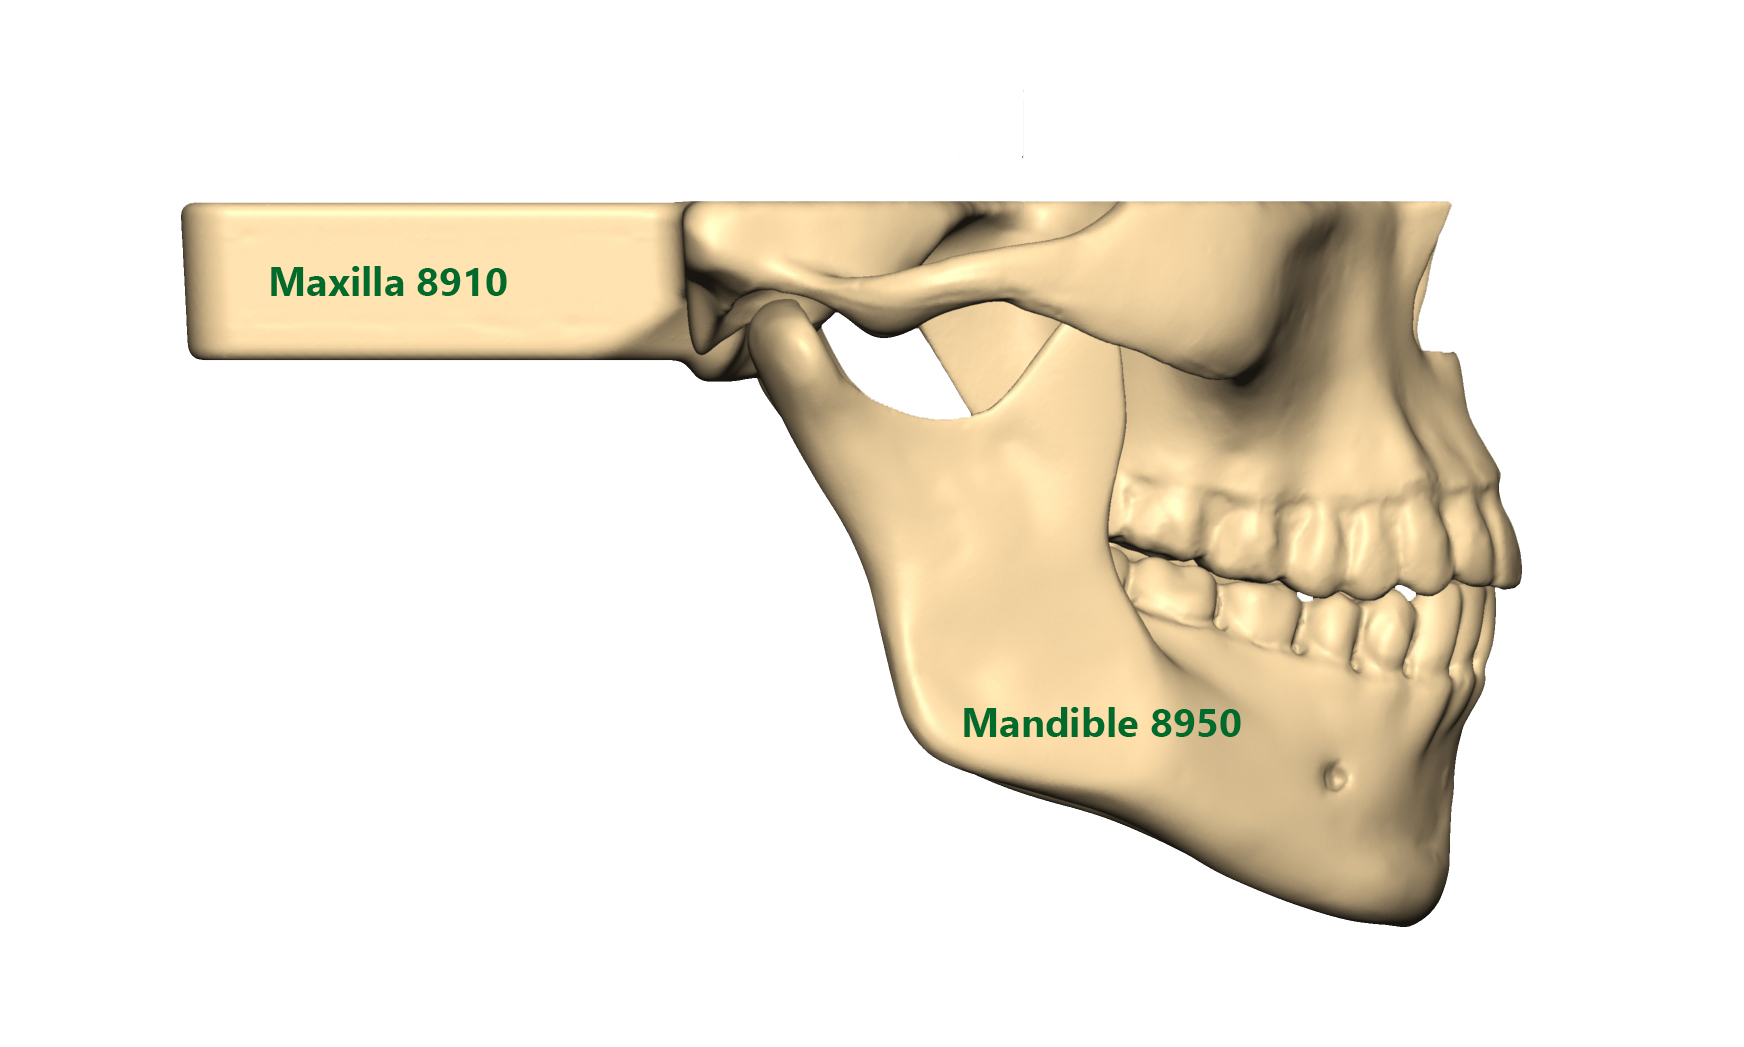

Mandible and Maxilla models with Easy Clip

SYNBONE’s new Mandible and Maxilla models with easy clip mechanism offer the highest flexibility when combining the products together. The Mandibles do also correspond to our 8200 / 8700 and 8800 Skull models.

You can choose from standard, overbite or underbite situations for your orthognathic surgery education. We offer intact, fractured or prefractured models for your LeFort I and BSSO workshops. Thanks to the drill holes between each tooth all models can be used for cerclage wiring.

Our Maxillas with Easy Clip mechanism correspond to the 8900 and 8950 Mandible series. Rubber brackets allow a firm hold of the mandibles.

All Mandibles with Easy Clip mechanism correspond to our 8200 / 8700 and 8800 Skull models as well as 8910 and 8915 Maxillas.

Reusable cerclage wiring alternative clip for Maxilla/Skull and Mandible fixation. Also ask for our regular / overbite and underbite OP-Splints.